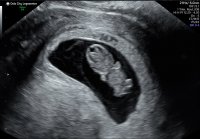

6+0, målene stemte med hvor langt jeg var på vei og vi fikk se et blinkende hjerte![]()

Fikk se et hjerte som banket. Det er jo ikke så mye å se så tidlig, og for tidlig til å sette termin sa legenVar på UL idag, min beregning var 7+4, noe som så ut til å stemme. Tok utvendig UL, jeg trodde de bare brukte innvendig frem til ca 12 uker. Fikk med et bildeFikk se et hjerte som banket. Det er jo ikke så mye å se så tidlig, og for tidlig til å sette termin sa legen

Nå er jeg 8+6 med nummer 2. Fikk se hjerte og sprelling i dag på TUL. Utrolig letter etter litt småblødninger og mye kramper![]()